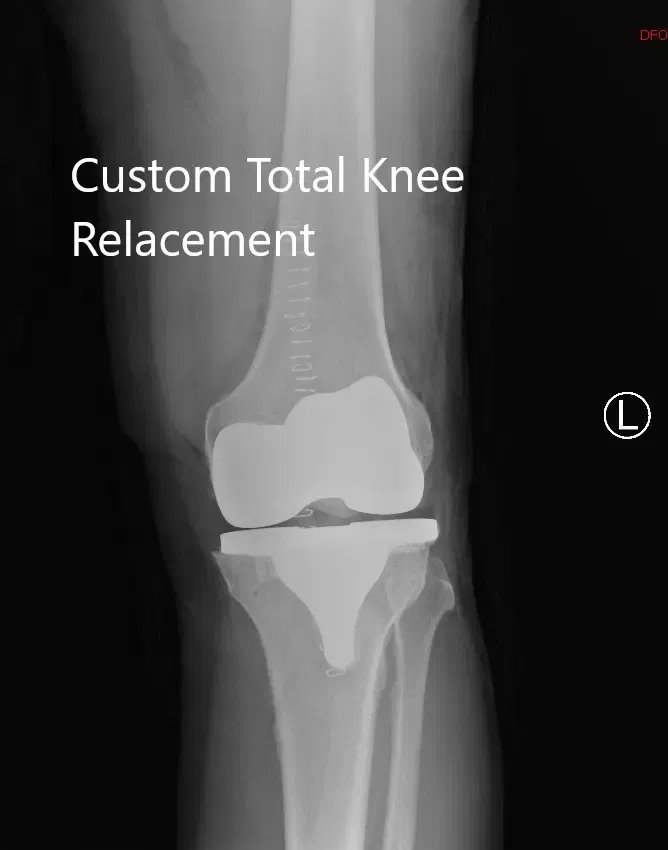

OPERACIÓN: Artroplastia total de rodilla izquierda usando implantes de rodilla personalizados. Los implantes utilizados fueron implantes femorales con una bandeja tibial personalizada con inserto de polietileno de 16 mm con

Implante rotuliano de 29 mm x 6 mm.

Radiografía postoperatoria de la rodilla izquierda que muestra vistas laterales y AP